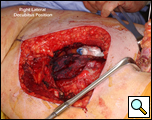

Eleven months later, he presented with a several month history of a painful fixed, firm mass over the pectoral area of the left chest and a smaller mass inferior to this (Figure 1). CT scan demonstrated a new 2 cm nodule in the left upper lobe associated with an anterior chest wall mass six centimeters in size in addition to bilateral new pulmonary nodules (Figure 2). The mass was tethered to the skin and in danger of eroding through it. The patient underwent en-bloc resection of the chest wall and adjacent lung (Figures 3a-c). The resulting defect (Figure 4a) was reconstructed with 2 mm Gore-Tex patch (Figure 4b) and pectoralis major muscle flap (Figure 4c) with primary skin closure (Figure 4d). The pathology revealed metastatic chordoma (Figures 5a-d). The patient recovered well, leaving the hospital on the sixth postoperative day.